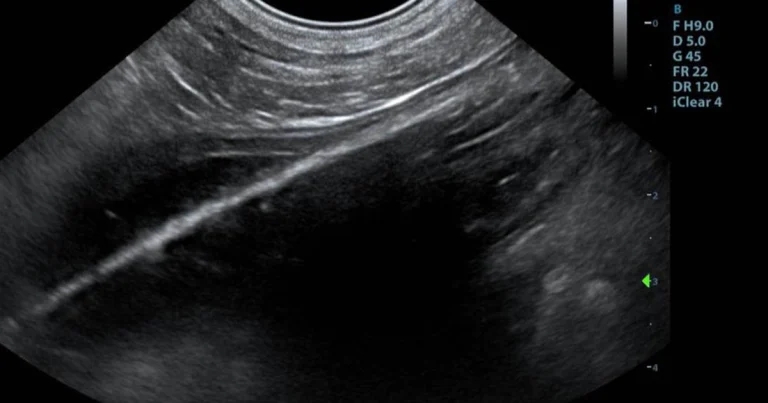

Figure 1. Ultrasound image of the foreign body.

An opacity was visible in the lumen of the jejunum. This object presented as a perfectly straight echogenic line, which did not change shape regardless of probe angle or pressure (Figure 1).

The appearance of intestinal foreign bodies varies depending on their acoustic impedance. Foreign bodies that produce strong acoustic shadowing may be more easily visible. Wooden foreign bodies, such as this one, often present as a linear echogenic structure with pronounced acoustic shadowing6.